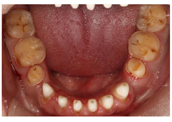

(1)面部检查:面部外形不对称,颏部居中,两侧口角高度不一致,面下1/3高度减小,两侧颧弓突度一致,下颌前突。中位笑线,上唇长度适中(图1)。(2)关节检查:颞颌关节:弹响(-),杂音(-),疼痛(-)。开口度正常,开口型有偏斜,肌肉触诊压痛:右侧上颌结节(+)、左侧上颌结节(++)、双侧翼内肌(+),其他肌肉及颞下颌关节区未诉异常,关节载荷实验无任何紧张和疼痛不适。(3)口内检查:上下颌牙中线较面中线向右偏斜,前后牙广泛不均匀磨耗,前牙磨耗后呈刃状;14、21、22、23及下颌牙唇颊侧颈部见釉质缺损,部分牙本质暴露,呈黄褐色,少量白垩色;44牙见开髓孔,表面暂封。12缺失,缺失牙间隙无。全口牙龈色形质未见异常,11牙、21牙唇侧牙龈龈缘高度不一致,21牙较11牙龈缘高约3mm。全口口腔卫生状况良好,菌斑、软垢少量,未及牙石及牙周袋。咬合检查:11-14牙与对颌牙反

,21牙与31、31牙对刃,左侧尖牙至前磨牙深覆盖,

曲线不平(图2,图3)。(4)影像学检查: